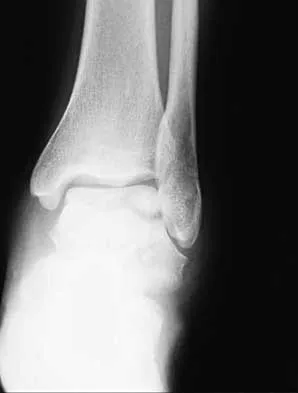

Figures 4a through 4c show the radiographs of a 43-year-old woman who sustained a twisting injury to her right ankle. She has ankle pain and tenderness medially and laterally. To help determine the optimal treatment, an external rotation stress radiograph of the ankle is obtained. This test is designed to evaluate the integrity of what structure?

Explanation

In the presence of a supination external rotation-type fracture of the distal fibula (Weber type B), stability of the ankle is best assessed by performing an external rotation stress AP view of the ankle. This test is used to assess the integrity of the deltoid ligament. The presence of a deltoid ligament rupture results in instability and generally is best managed surgically. The gravity stress test can also be used. Egol KA, Amirtharajah M, Tejwani NC, et al: Ankle stress test for predicting the need for surgical fixation of isolated fibular fractures. J Bone Joint Surg Am 2004;86:2393-2398. McConnell T, Creevy W, Tornetta P III: Stress examination of supination external rotation-type fibular fractures. J Bone Joint Surg Am 2004;86:2171-2178.